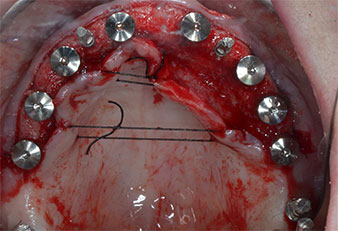

Trois ans après, le moment était venu pour elle de se doter d’une prothèse maxillaire du même type. Sur la base de la planification CBCT, l’élévation sinusale a été évitée grâce à la pose d'implants courts, et un gabarit chirurgical a été utilisé pour transférer les positions planifiées sur la crête alvéolaire (Figures 1 et 2).

Compte tenu de la dureté relative de l’os (D2) à cet endroit, les sites recevant des implants de 10mm de long aux régions 11 et 21 ont été finalisés à l'aide d’une fraise de 4mm de diamètre, associée à un contre-angle chirurgical W&H WS-75 L, au moteur d'implantologie Implantmed de W&H ainsi qu’au module Osstell ISQ de W&H. En revanche, en raison de leur structure osseuse molle, les sites postérieurs ont été préparés en vue de l’obtention d’un diamètre final de 3mm à l'aide de l’insert Piezomed I3P. Les implants ont enfin été posés par voie transgingivale (Flap Less) pour obtenir l’ostéointégration dans un délai de trois mois (Figures 6-10). L'appareil existant a été maintenu sur quatre implants provisoires (Fig. 8).